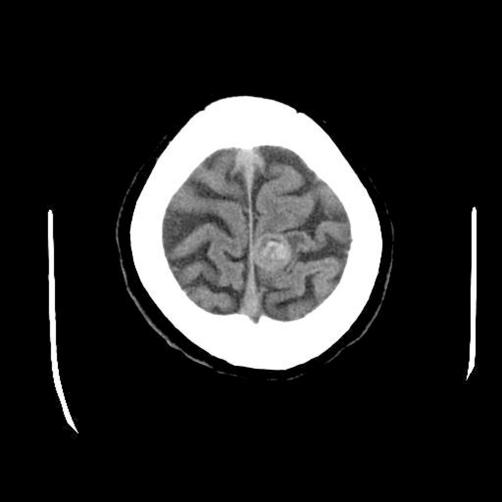

The author reports herein a case of occult very small lung carcinoma with a solitary brain metastasis that is clinically diagnosed as cavernous hemangioma, with an emphasis on pathologic findings. A 48-year-old Japanese man was admitted to our hospital complaining of mild paresis of left leg. Brain CT and MRI showed a solitary tumor (2 cm) with features of cavernous hemangioma in the right temporal lobe. Tumorectomy was performed, and it was pathologically undifferentiated carcinoma. An immunohistochemical analysis reveled that the carcinoma cells were positive for four types of pancytokeratin, cytokeratin (CK) 5/6, CK7, CK18, CK19, p63, and Ki-67 (78%). They were negative for high molecular weight CK, CK14, CK20, TTF-1, PE-10, melanosome, S100 protein, EMA, vimentin, CD34, myoglobin, CEA, p53, desmin, alpha-smooth muscle actin, chromogranin, synaptophysin, CD56, neuron-specific enolase, CD68, KIT, and PDGFRA. The positive CK7 and negative CK20 suggested lung origin, and cytokeratin profiles and positive CK5/6 and p63 suggested a squamous differentiation. The pathological diagnosis was undifferentiated carcinoma with squamous differentiation probably of lung origin. Later, systemic CT, MRI and PET were performed, and they detected a small lung tumor (8 mm) in the right apex. The lung biopsy revealed an undifferentiated carcinoma with focal squamous differentiation; the immunohistochemical findings were the same as those of the brain tumor. These findings suggest that occult very small lung carcinoma can metastasize to brain and such a metastasis may mimic cavernous hemangioma radiologically. Pathologic observations using many antibodies are very useful to determine the origin and histological type in solitary brain nodule.

本文作者报告了一例隐匿性微小肺癌伴孤立性脑转移瘤的病例,该脑转移瘤临床诊断为海绵状血管瘤,重点介绍其病理表现。一名48岁的日本男性因左腿轻度无力入院。脑部CT和MRI显示右颞叶有一个具有海绵状血管瘤特征的孤立性肿瘤(2厘米)。行肿瘤切除术,病理检查为未分化癌。免疫组化分析显示,癌细胞对四种全细胞角蛋白、细胞角蛋白(CK)5/6、CK7、CK18、CK19、p63和Ki-67(78%)呈阳性。它们对高分子量CK、CK14、CK20、TTF-1、PE-10、黑素体、S100蛋白、EMA、波形蛋白、CD34、肌红蛋白、CEA、p53、结蛋白、α-平滑肌肌动蛋白、嗜铬粒蛋白、突触素、CD56、神经元特异性烯醇化酶、CD68、KIT和PDGFRA呈阴性。CK7阳性和CK20阴性提示肺来源,细胞角蛋白谱以及CK5/6和p63阳性提示鳞状分化。病理诊断为可能起源于肺的伴鳞状分化的未分化癌。后来,进行了全身CT、MRI和PET检查,发现右肺尖有一个小的肺部肿瘤(8毫米)。肺活检显示为伴有局灶性鳞状分化的未分化癌;免疫组化结果与脑肿瘤相同。这些发现表明,隐匿性微小肺癌可转移至脑部,且这种转移在影像学上可能类似海绵状血管瘤。使用多种抗体进行病理观察对于确定孤立性脑结节的起源和组织学类型非常有用。